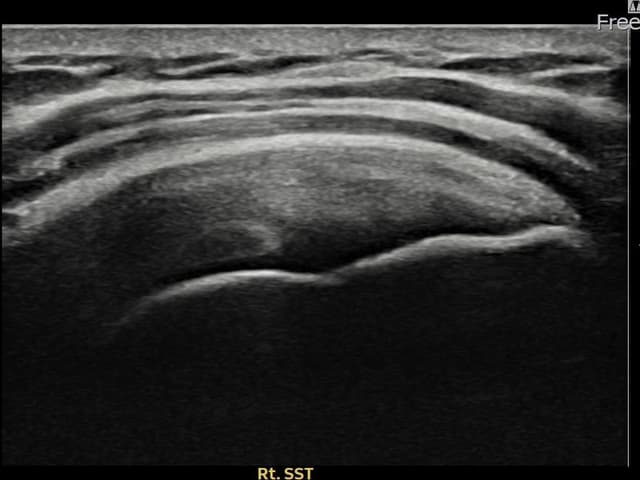

[経過期間: 24.07.29~24.10.07]

[縫縮術] 超音波検査にて右 棘上筋腱 関節面側部分断裂(12mm × 4mm (腱厚の約48%欠損))を確認。縫縮術施行後、腱の連続性が回復し、日常生活に復帰されました。

[経過期間: 24.08.19~24.10.28]

[縫縮術] 超音波検査にて右 棘上筋腱 関節面側部分断裂(10mm × 4mm (腱厚の約40%欠損))を確認。縫縮術施行後、腱の連続性が回復し、日常生活に復帰されました。